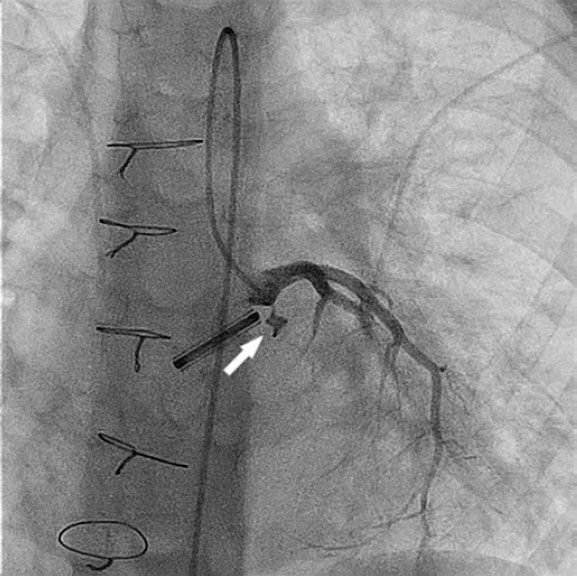

Initial aortography did not demonstrate a paravalvular leak but revealed dilation of the left main coronary artery (6.5 mm) and a coronary–left ventricular fistula measuring 2.4 mm in diameter and 4.5 mm in length (figure 1 and video S1).

Figure 1.